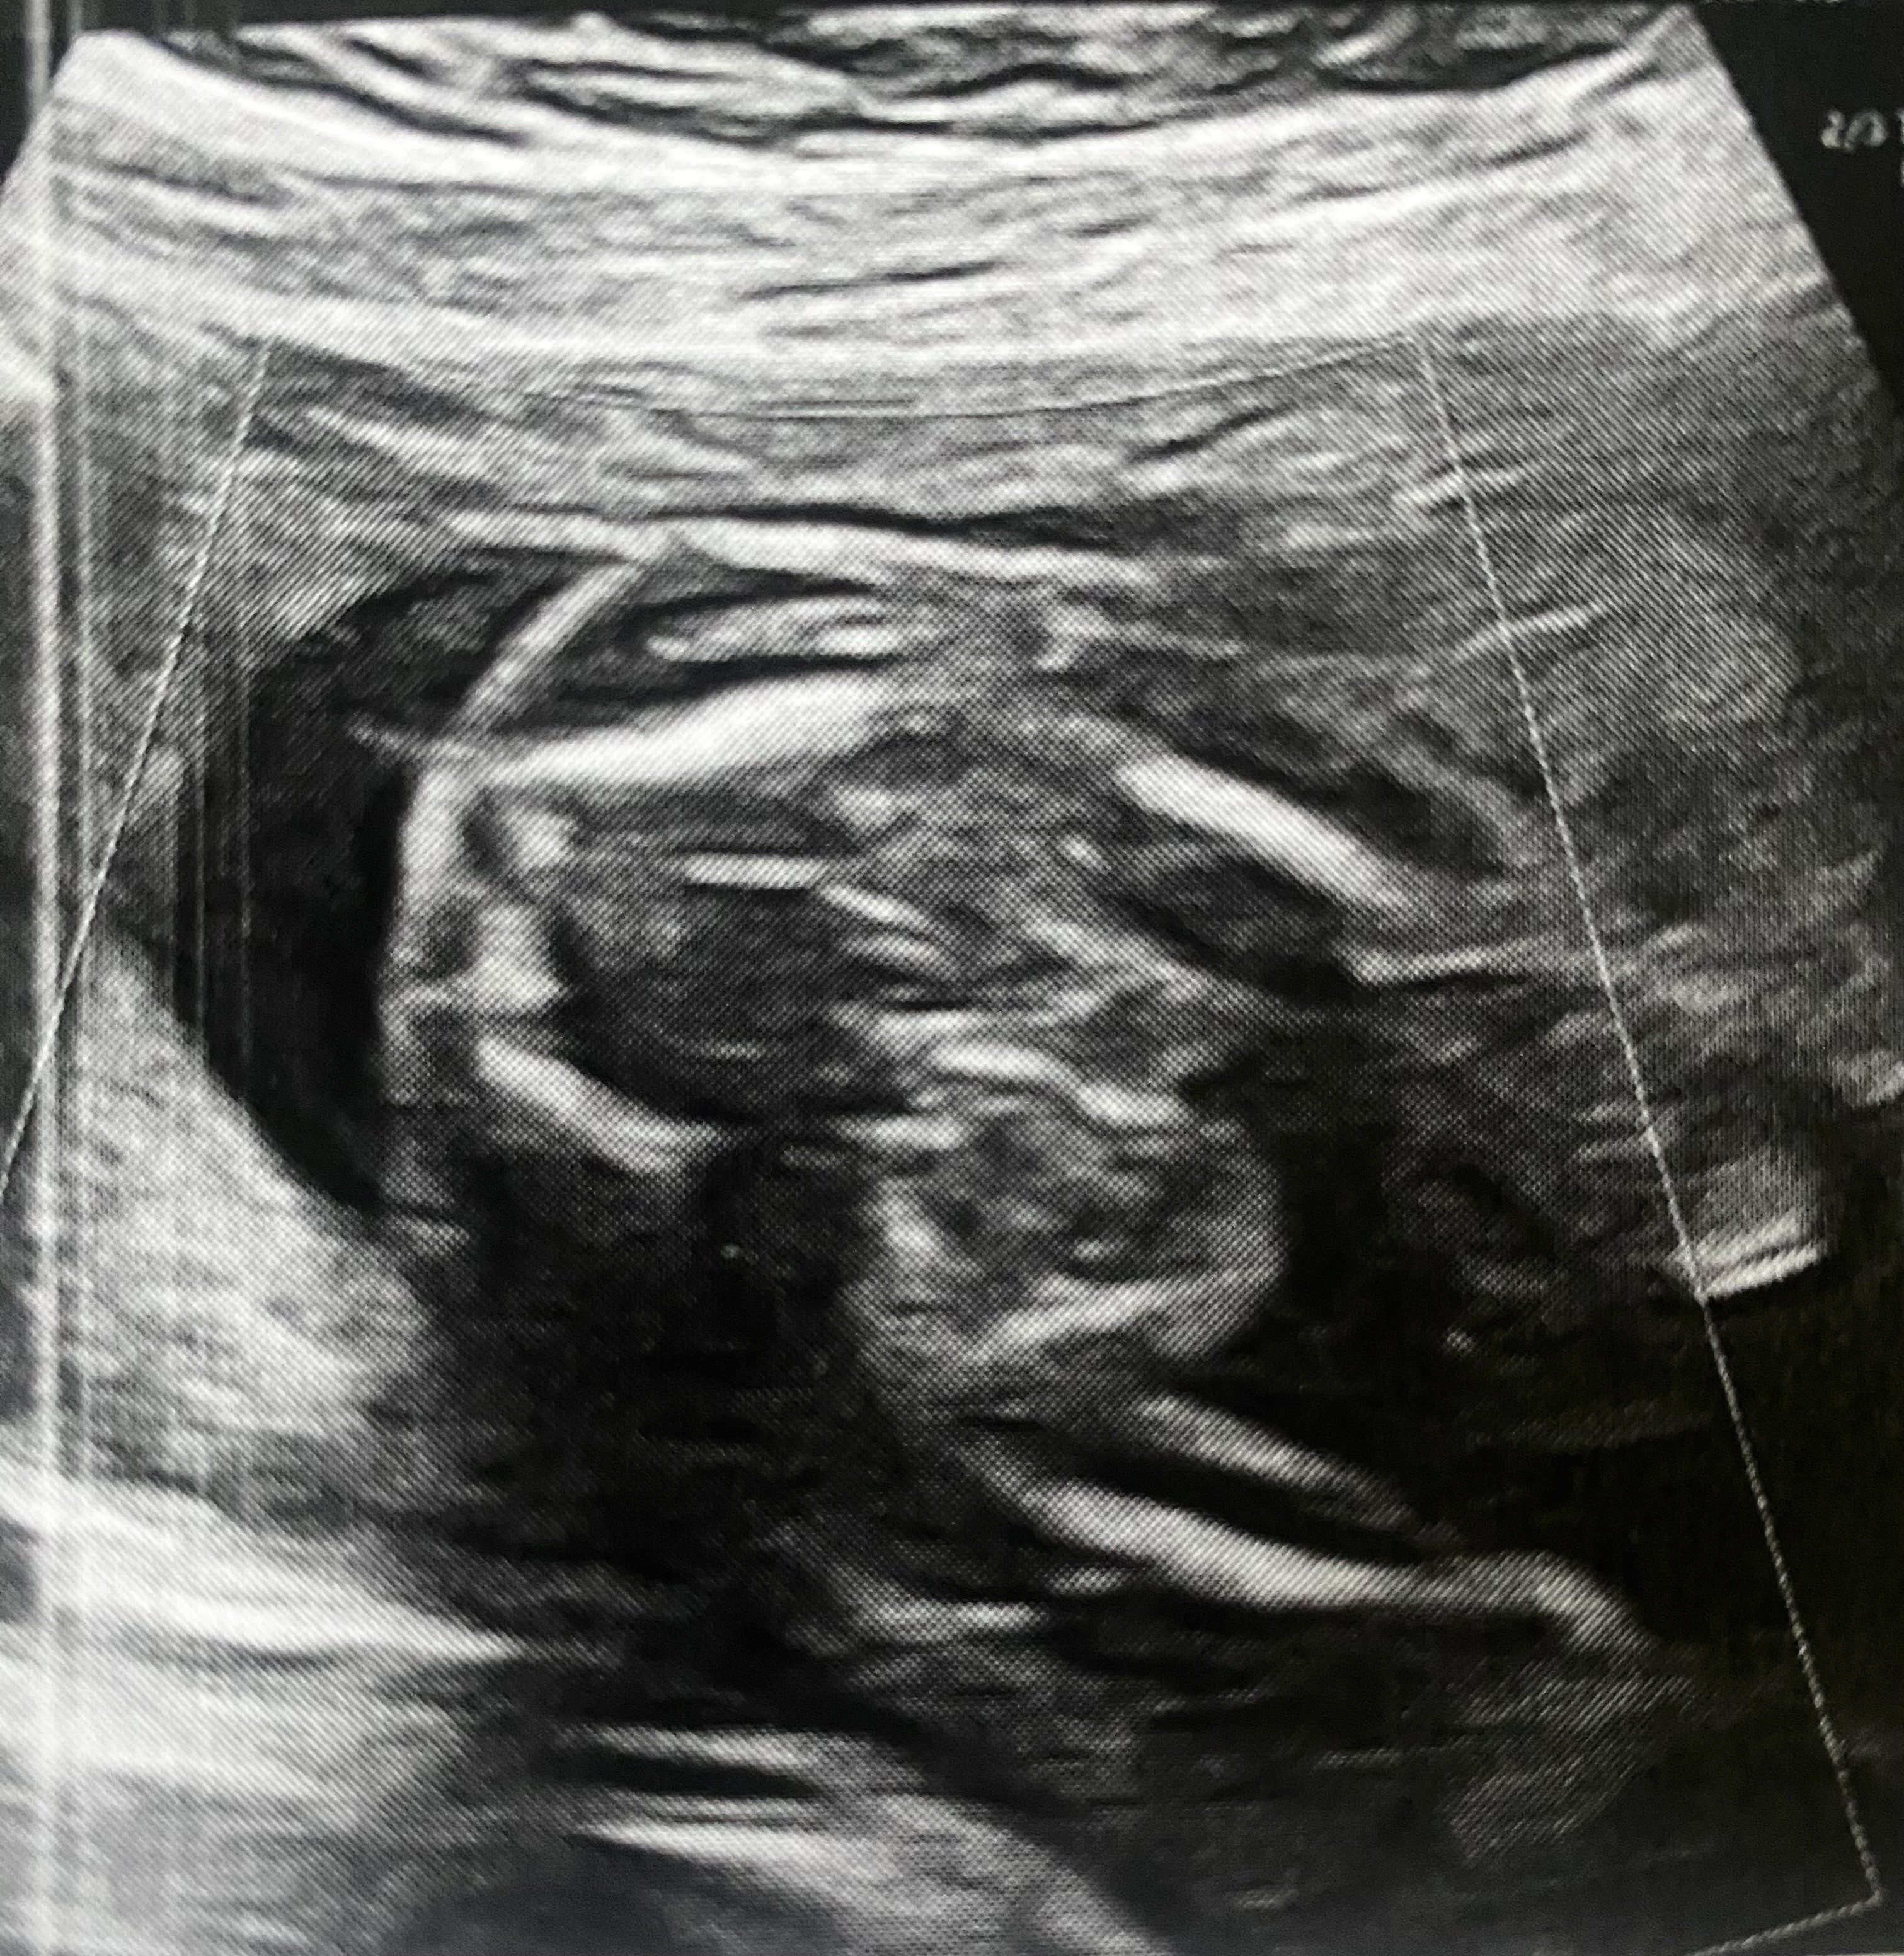

Cześć dziewczyny,

Dziewczynka czy chłopiec?